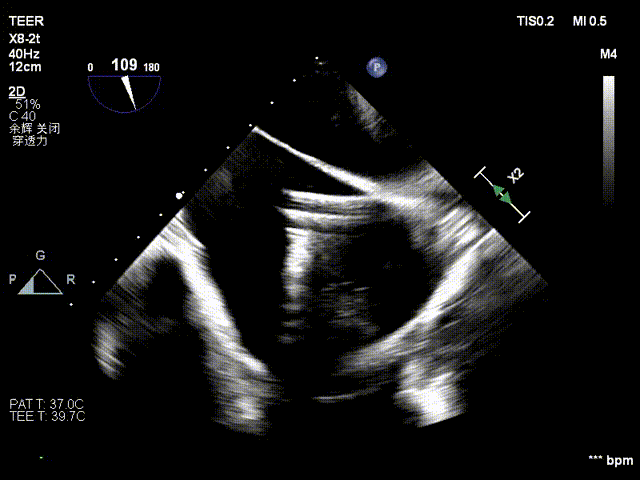

术前食道超声评估:三尖瓣重度反流,FTR6+,反流位于前隔、中央,后隔。瓣叶粘液样变性,后隔可见4.6mm gap。

麻醉后基线反流

视频1:术前Bicom